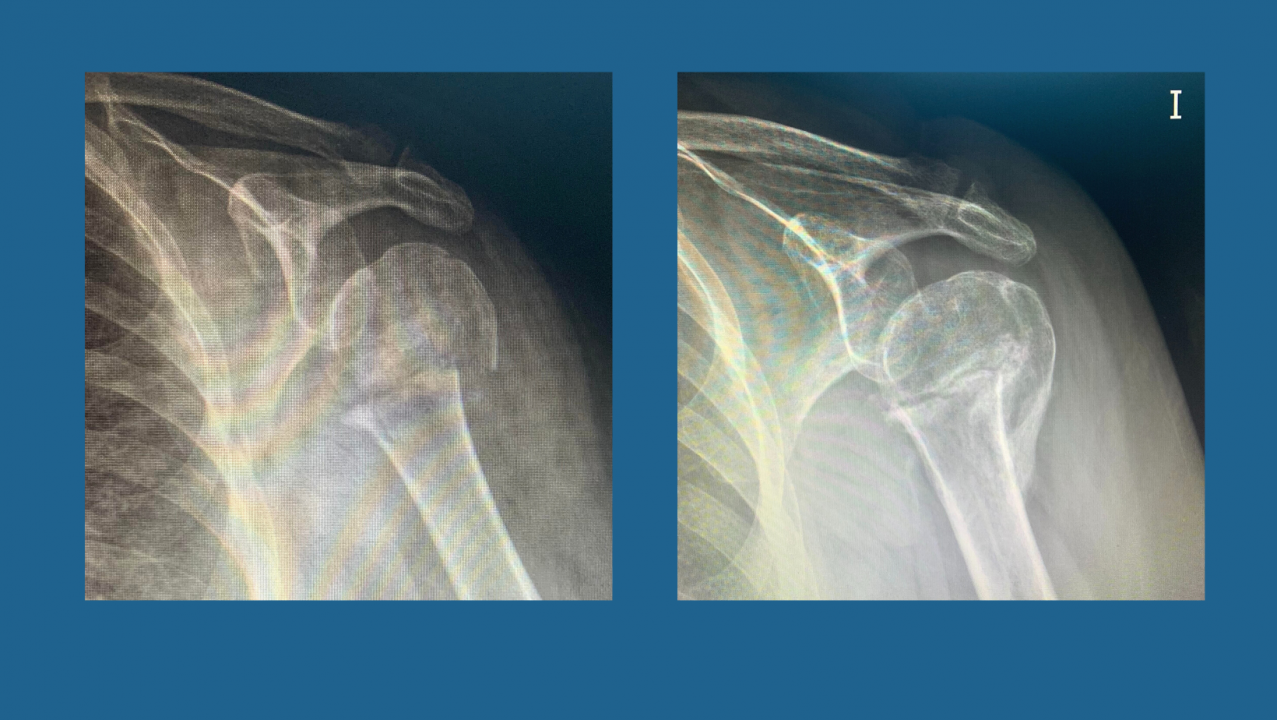

Os presentamos un caso tratado en Trauma Sport con Magnetoterapia. Paciente de 74 años que sufre una caída desde su propia altura generando una fractura de baja energía a nivel del cuello del húmero, en el hombro izquierdo. Acude a nuestra clínica en Ourense 3 meses después del diagnóstico con una imagen radiológica (Fig. 1) en la que vemos claramente como la fractura no ha consolidado; y con el tiempo tanscurrido puede considerarse un retardo de consolidación. La paciente no podía retirar el cabestrillo, tenía dolor que no calmaba con tratamientos convencionales, además de dificultad para el descanso nocturno.Angustiada a su vez, porque le habían comentado que dado que no había pegado la fractura deberían someterla a una cirugía con placa y tornillos, e injerto óseo.

Se comienza con tratamiento de Magnetoterapia durante un mes asociado a terapia manual para el resto de limitaciones en el miembro superior izquierdo que tenía por la inmovilización tan prolongada. Con un mes de tratamiento se realiza un estudio radiológico (Fig. 2) que demuestra que la fractura ha generado un callo, consiguiendo la consolidación suficiente para comenzar a mover su hombro y, sin necesidad de tratamiento con antiinflamatorios, pudo descansar por las nochces sin tener que levantarse por el dolor nocturno. Con todo ello, con la combinación de la Magnetoterapia y la Terapia Manual hemos evitado una cirugía a la paciente.